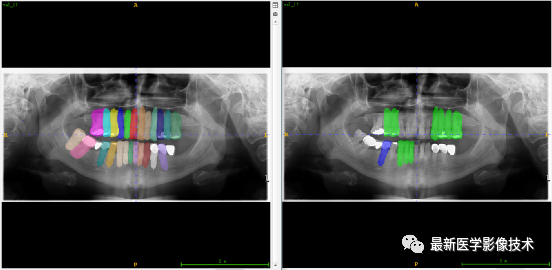

验证集牙齿分割计数和异常牙齿分割识别

左图是分割计数,右图是异常牙齿分割识别结果